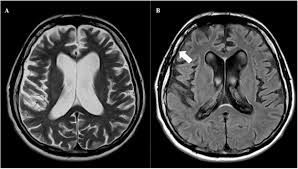

Symptoms of neurosyphilis

This form of the disease usually shows up anywhere from a few weeks to a few years after a person contracts syphilis. Symptoms include: nausea vomiting a stiff neck a headache It may also cause a loss of hearing or vision.